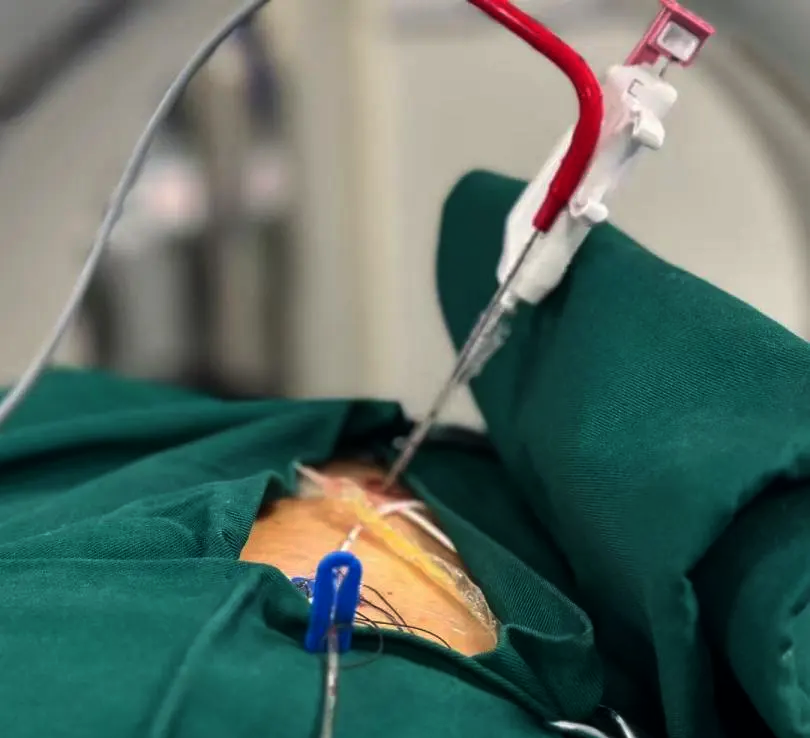

三秦都市报-三秦网讯(记者 阮班慧)一根细针,超低温能量,10分钟快速病理诊断,术后仅留针眼创口——西安市大兴医院呼吸与危重症医学科团队通过创新技术,为肺部肿瘤治疗带来新突破。记者获悉,自2024年起,该院劳动北路院区已率先在陕西开展CT影像联合病理现场快速细胞学技术(ROSE)辅助下的肺结节冷冻消融治疗,实现

作为国家肿瘤微创介入中心建设单位,西安大兴医院自2023年起已先后完成肺癌、肝癌、乳腺癌等8类肿瘤微创治疗。此次技术升级聚焦肺部结节治疗:通过消融针穿刺,将超低温能量传递作用在肺结节上,直接把实体结节(肿瘤)“冻死”,以遏制其发展和扩散,术后只留下一个“针眼”大小的创口。

“传统手术创伤大、恢复慢,而冷冻消融创伤极小,患者术后当天即可下床活动。”该院呼吸与危重症医学科穆德广主任介绍,该技术有利于精准定位与诊断,提高治疗效果,减少并发症与风险,缩短治疗时间与住院周期,增强患者舒适度。该技术尤其适合高龄、体弱或无法耐受开放手术的患者。

为确保疗效,西安大兴医院团队创新融合CT影像引导与ROSE快速诊断技术。精准定位:CT实时引导穿刺路径,明确结节位置及性质,避免误伤周围组织;快速诊断:术中同步进行活检,病理科医生通过ROSE技术,10分钟内出具病理结果,明确良恶性及范围,指导消融方案;实时监测:全程可视化操作,动态调整消融边界,最大限度保护正常肺组织。

“过去需要等待3-5天的病理报告,现在术中即可确诊。”穆德广团队已累计完成50余例冷冻消融治疗,其中20余例联合ROSE技术,患者平均住院周期缩短至3天。